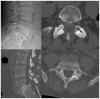

Purpose: The primary purposes of the study were to evaluate the prevalence of lumbar spine degeneration features, evaluated on computed tomography (CT), in a community-based sample and to evaluate the association between lumbar spine degeneration features. The secondary purpose was to evaluate the association between spinal degeneration features and LBP.

Outcome measures: Self-report measures: LBP in the preceding 12 months was evaluated using a Nordic self-report questionnaire. Physiologic measures: Dichotomous variables indicating the presence of intervertebral disc narrowing, facet joint osteoarthritis (OA), spondylolysis, spondylolisthesis, and spinal stenosis and the density (in Hounsfield units) of multifidus and erector spinae muscles were evaluated on CT.

Results: In total, 104 men and 83 women, with a mean age (+/-standard deviation) of 52.6+/-10.8 years, participated in the study. There was a high prevalence of intervertebral disc narrowing (63.9%), facet joint OA (64.5%), and spondylolysis (11.5%) in the studied sample. When all spinal degeneration features as well as age, sex, and BMI were factored in stepwise fashion into a multiple logistic regression model, only spinal stenosis showed statistically significant association with LBP, odds ratio (OR) (95% confidence interval [CI]): 3.45 [1.12-10.68]. Significant association was found between facet joint OA and low density of multifidus (OR [95% CI]: 3.68 [1.36-9.97]) and erector spinae (OR [95% CI]: 2.80 [1.10-7.16]) muscles.